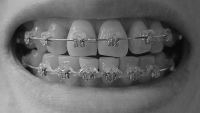

奥に引っ張るのは前歯の隙間を詰めてからにするとかなんとか言い出して、ワイヤー交換して前の歯にパワーチェーン(だと思う)を付けて終了。

しかもワイヤーをもう一段太くしようとして、ブラケットに無理やり押し込んで抜けなくなり、顎をギシギシいわせながらぐいぐい引っ張られました。以前にも同じことやってんのよね、この先生。

その後、何事もなかったようにワイヤーを付け始めたので抜けたのか?と思っていたのですが、終わってから見てみたら、刺さったワイヤーはそのままで、交換したワイヤーがブラケットに細い針金で固定されてました

まぁほんまに、ないんやろうけどなぁ。奥に引っ張るのは前歯の隙間を詰めてからにするとかなんとか言い出して、ワイヤー交換して前の歯にパワーチェーン(だと思う)を付けて終了。